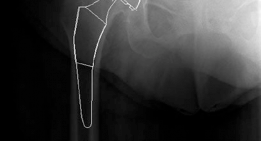

Clinical & Radiographic Imaging